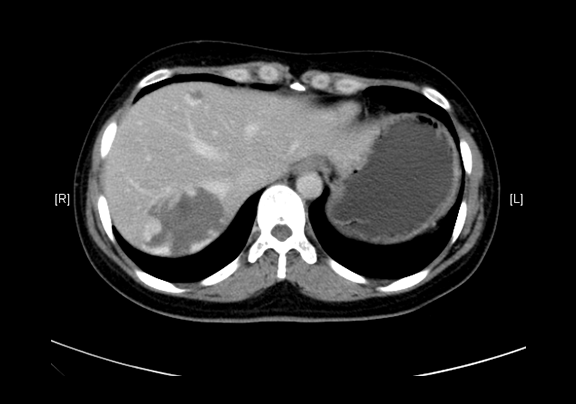

平衡期